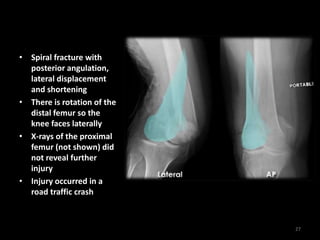

• Spiral fracture with

posterior angulation,

lateral displacement

and shortening

• There is rotation of the

distal femur so the

knee faces laterally

• X-rays of the proximal

femur (not shown) did

not reveal further

injury

• Injury occurred in a

road traffic crash

27